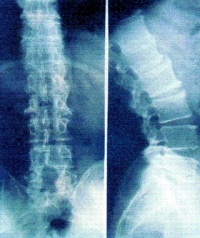

X线检查对AS的诊断有极为重要的意义,约98%~100%病例早期即有骶髂关节的X线改变,是本病诊断的重要依据。

早期X线表现为骶髂关节炎,病变一般在骶髂关节的中下部开始,为两侧性。开始多侵犯髂骨侧,进而侵犯骶骨侧。可见斑点状或块状骨侧明显。继而可侵犯整个关节,边缘呈锯齿状,软骨下有骨硬化骨质增生,关节间隙变窄。最后关节间隙消失,发生骨性强直。骶髂关节炎X线下易用按钮约诊断标准分类5级:0级为正常骶髂关节,Ⅰ级为可疑骶髂关节两侧炎;Ⅱ级为骶髂关节边缘模糊,略有硬化和微小侵蚀病变,关节腔轻度变窄;Ⅲ级为骶髂关节两侧硬化,关节边缘模糊不清,有侵蚀病变伴关节腔消失;Ⅳ级为关节完全融合或强直伴或不伴残存的硬化。

脊柱病变的X线表现,早期为普遍性骨质疏松,椎小关节及椎体骨小梁模糊(脱钙),由于椎间盘纤维环附带部椎骨上角和下的破坏性侵蚀,椎体呈“方形椎”,腰椎的正常前弧度消失而变直,可引起一个或多个椎体压缩性骨折。病变发展至胸椎和颈椎椎间小关节,间盘间隙发生钙化,纤维环和前纵行韧带钙化、骨化、韧带骨赘形成,使相邻椎体连合,形成椎体间骨桥,呈最有特征的“竹节样脊柱”。